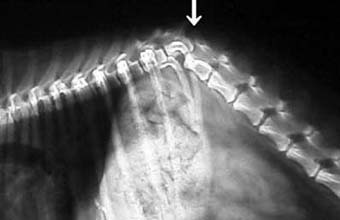

体重1.2kgの猫の脛骨(下腿骨)骨折。

これもピンニングと創外固定をタイインという方法で組み合わせることで、骨折部にメスを入れることなく整復固定しました。

写真上段: 手術前

写真2段目: 手術直後

写真3段目: 手術直後の様子

レーザーでピン刺入部に小さな穴を開けただけで骨折部を開創せず、手術負担が少なかったため、手術直後には着地歩行していました。

写真下段: 抜ピン後